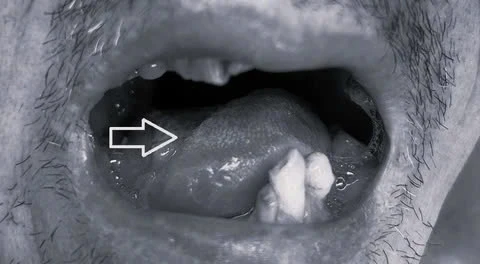

ung-thu-luoi2.jpg

Vị trí ung thư lưỡi của bệnh nhân. Ảnh: BVCC

Qua thăm khám, làm các xét nghiệm và chẩn đoán hình ảnh, các bác sĩ ghi nhận bệnh nhân có u ở thân lưỡi phải, kích thước 4x3 cm, nhiễm cứng, lồi lõm không đều, loét, dễ chảy máu, nhiều giả mạc, xâm lấn dính vào sàn miệng.

Lưỡi bị hạn chế vận động, làm bệnh nhân nuốt khó và nói không rõ, rất bất tiện trong sinh hoạt. Thêm nữa, bệnh nhân có hạch di căn dưới hàm phải, kích thước 7 mm, hình tròn, bờ trơn láng, mật độ chắc, không dính da, ấn không đau.